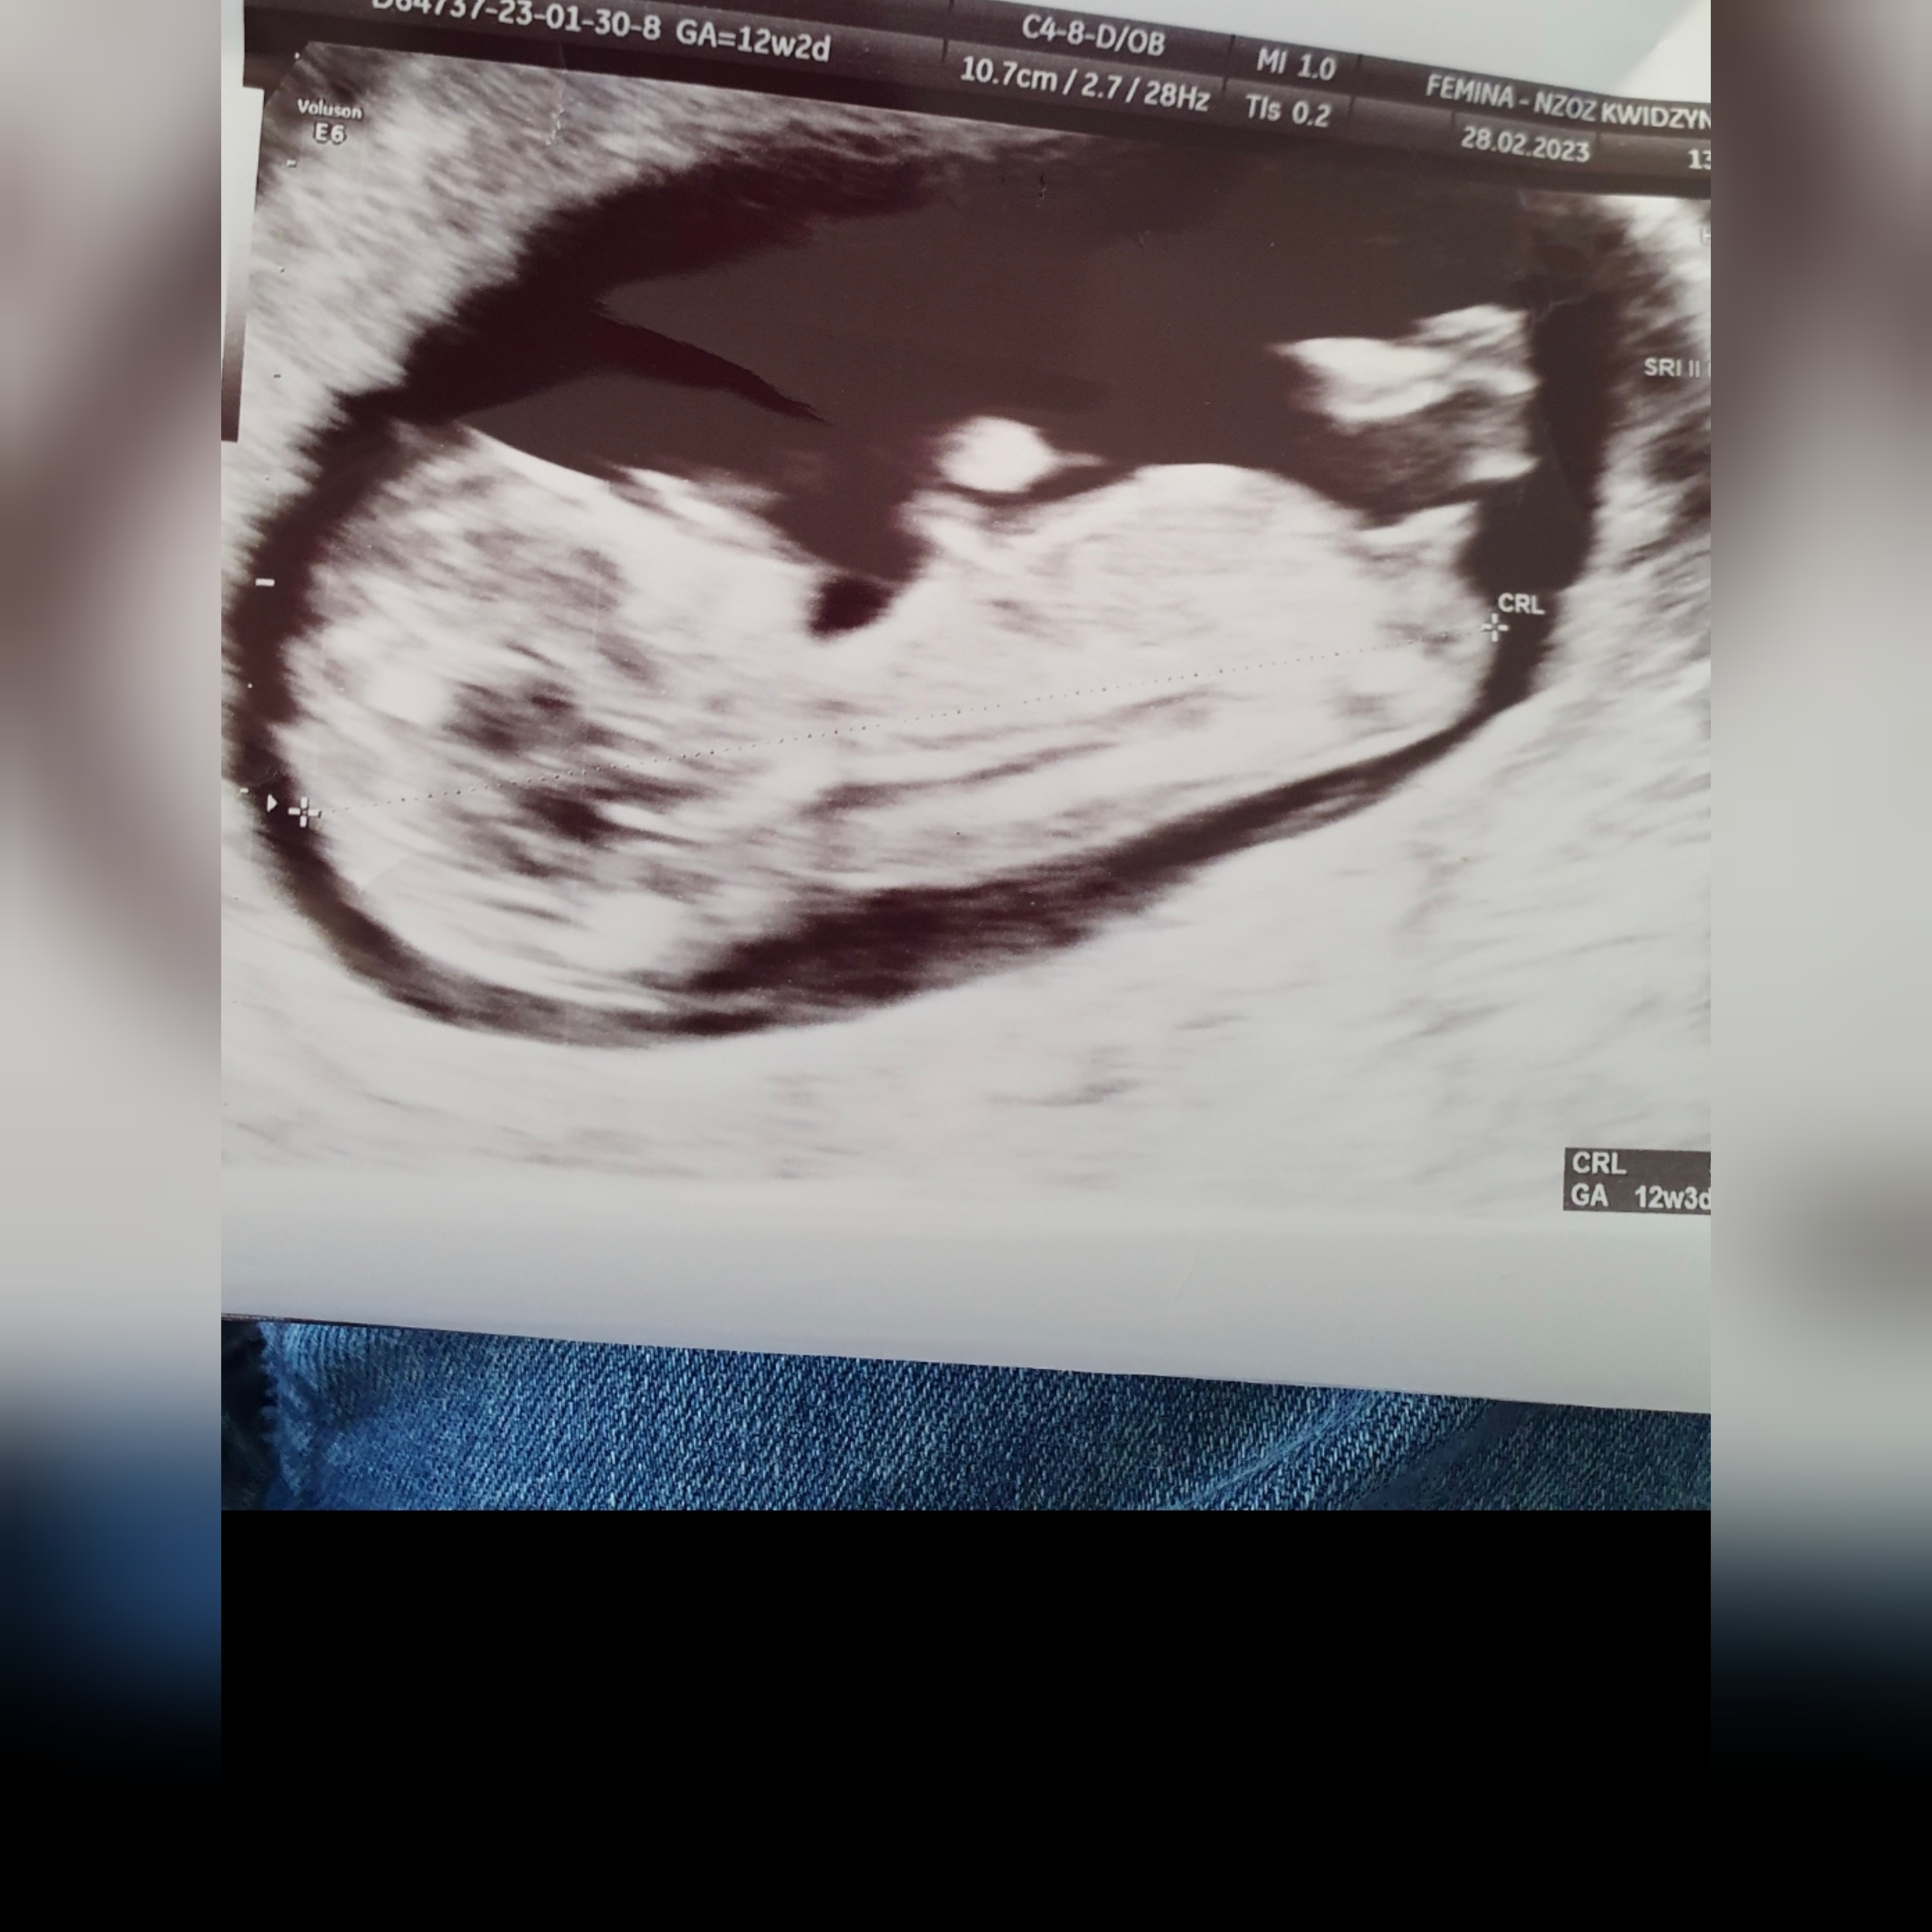

Chłopiec czy dziewczynka?

U mnie z takiego zdjęcia jest piękny chłopczyk. Myślę że u ciebie też będzie chlopiec. Pozdrawiam

Wyrostek na tym zdjęciu jest zupełnie inaczej ułożony niż na zdjęciu autorki :D Tutaj ewidentnie jest skierowany do góry jak u chłopczyka a u autorki na dwoje babka wróżyła moim zdaniem :D Możliwe, że u autorki za tydzień już będzie wyglądał jak u Ciebie, ale może też być dziewczynka moim zdaniem :D

U córki w 12+6 wyrostek był króciutki albo takie zdjęcie się akurat zrobiło 🤷🏼‍♀️ Syn z kolei miał taką jakby kuleczkę na końcu, więc też inaczej :D

Moje zdjęcie z 12+5, lekarz był pewny że chłopiec i się potwierdziło 🙂